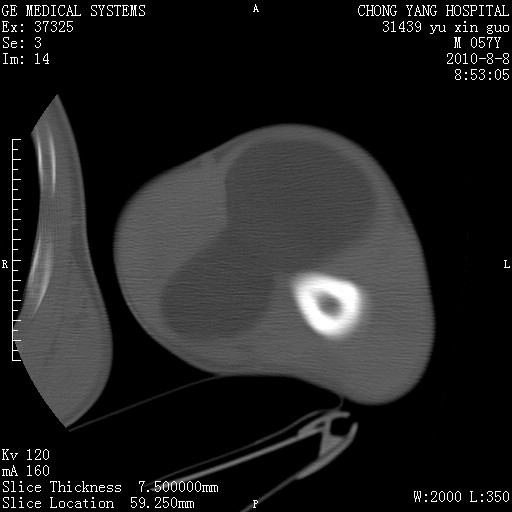

标题: CT28267:M57Y 上臂包块8年余。 [打印本页]

标题: CT28267:M57Y 上臂包块8年余。

典型脂肪瘤改变

包膜光滑、完整的脂肪密度肿块,支持脂肪瘤。